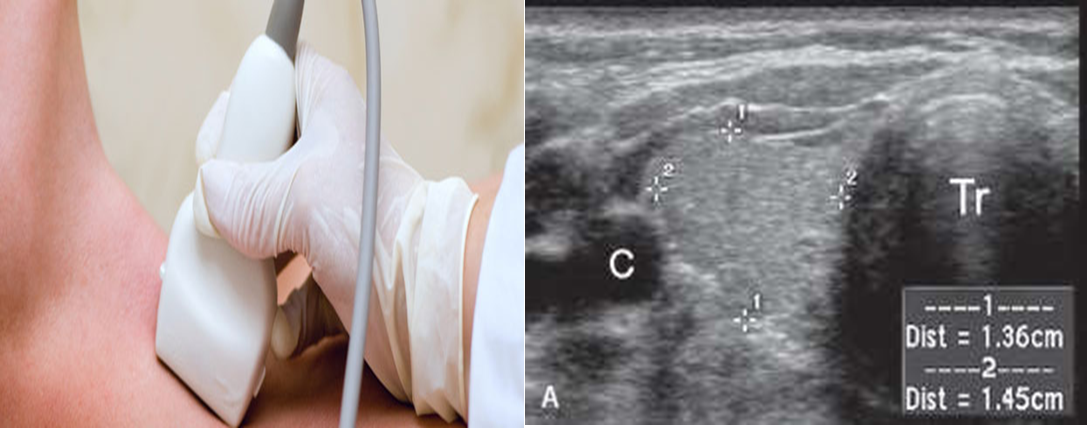

Ultrasound thyroid (transverse plane)

Normal image of the thyroid gland at the level of the isthmus.

1: right common carotid artery

2: right lobe

3: trachea

4: left lobe

5: left common carotid artery

6: left jugular vein

7: isthmus

Both right ,left lobes and isthmus are examined .Color Doppler is used to see vascularity. Ultrasound shows anatomical detail of thyroid and adjacent blood vessels and structures.

Normal parenchyma: homogeneous medium to high level echoes compared to adjacent neck muscles.